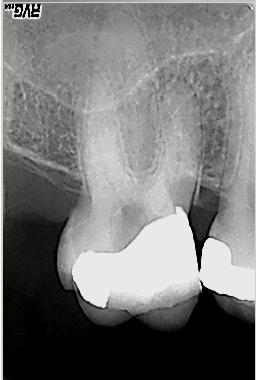

WF-Langzeitkontrolle

WF-Langzeitkontrolle nach 5 Monaten im November 2003. Als abschließende, für den Langzeiterfolg zwingend notwendige Maßnahme ist nun die Überkronung des Zahnes geplant